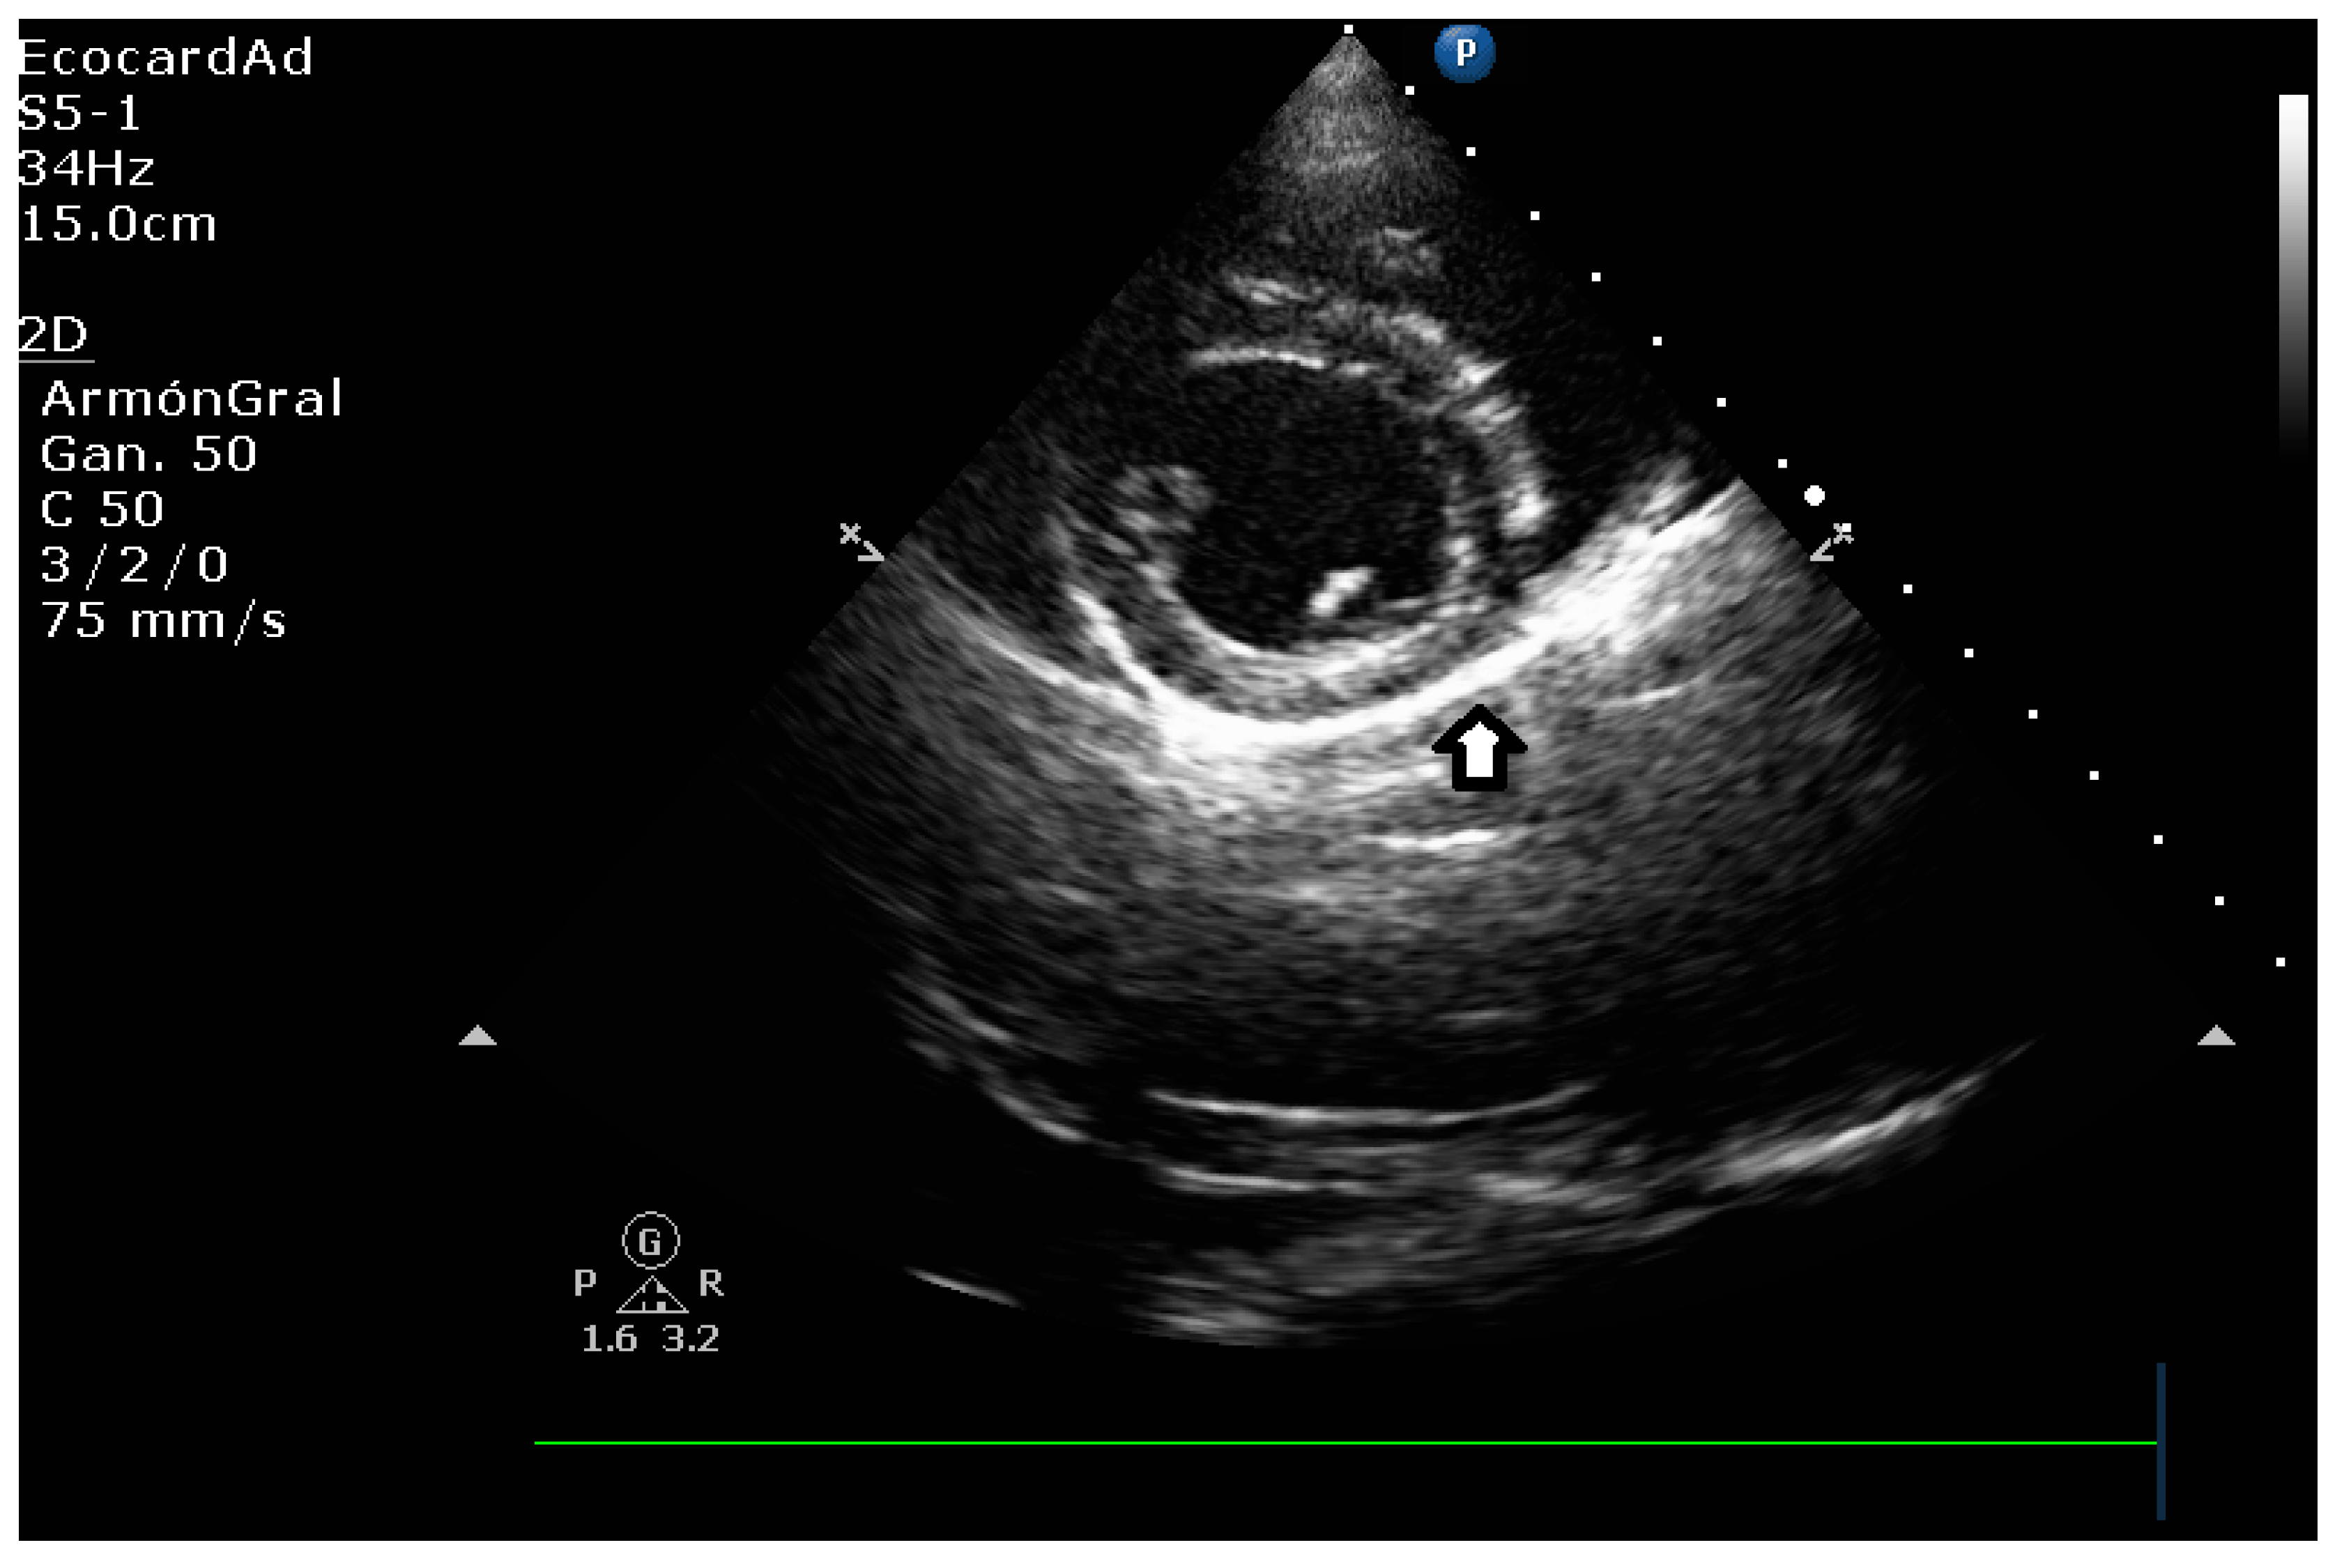

4.3. Canine Myxomatous Mitral Valve Disease. Comparative Transthoracic Echocardiography with Human Mitral Valve Prolapse

4.8.3. Degree of Myxomatous Degeneration

4.8.4. Mitral Valve Prolapse